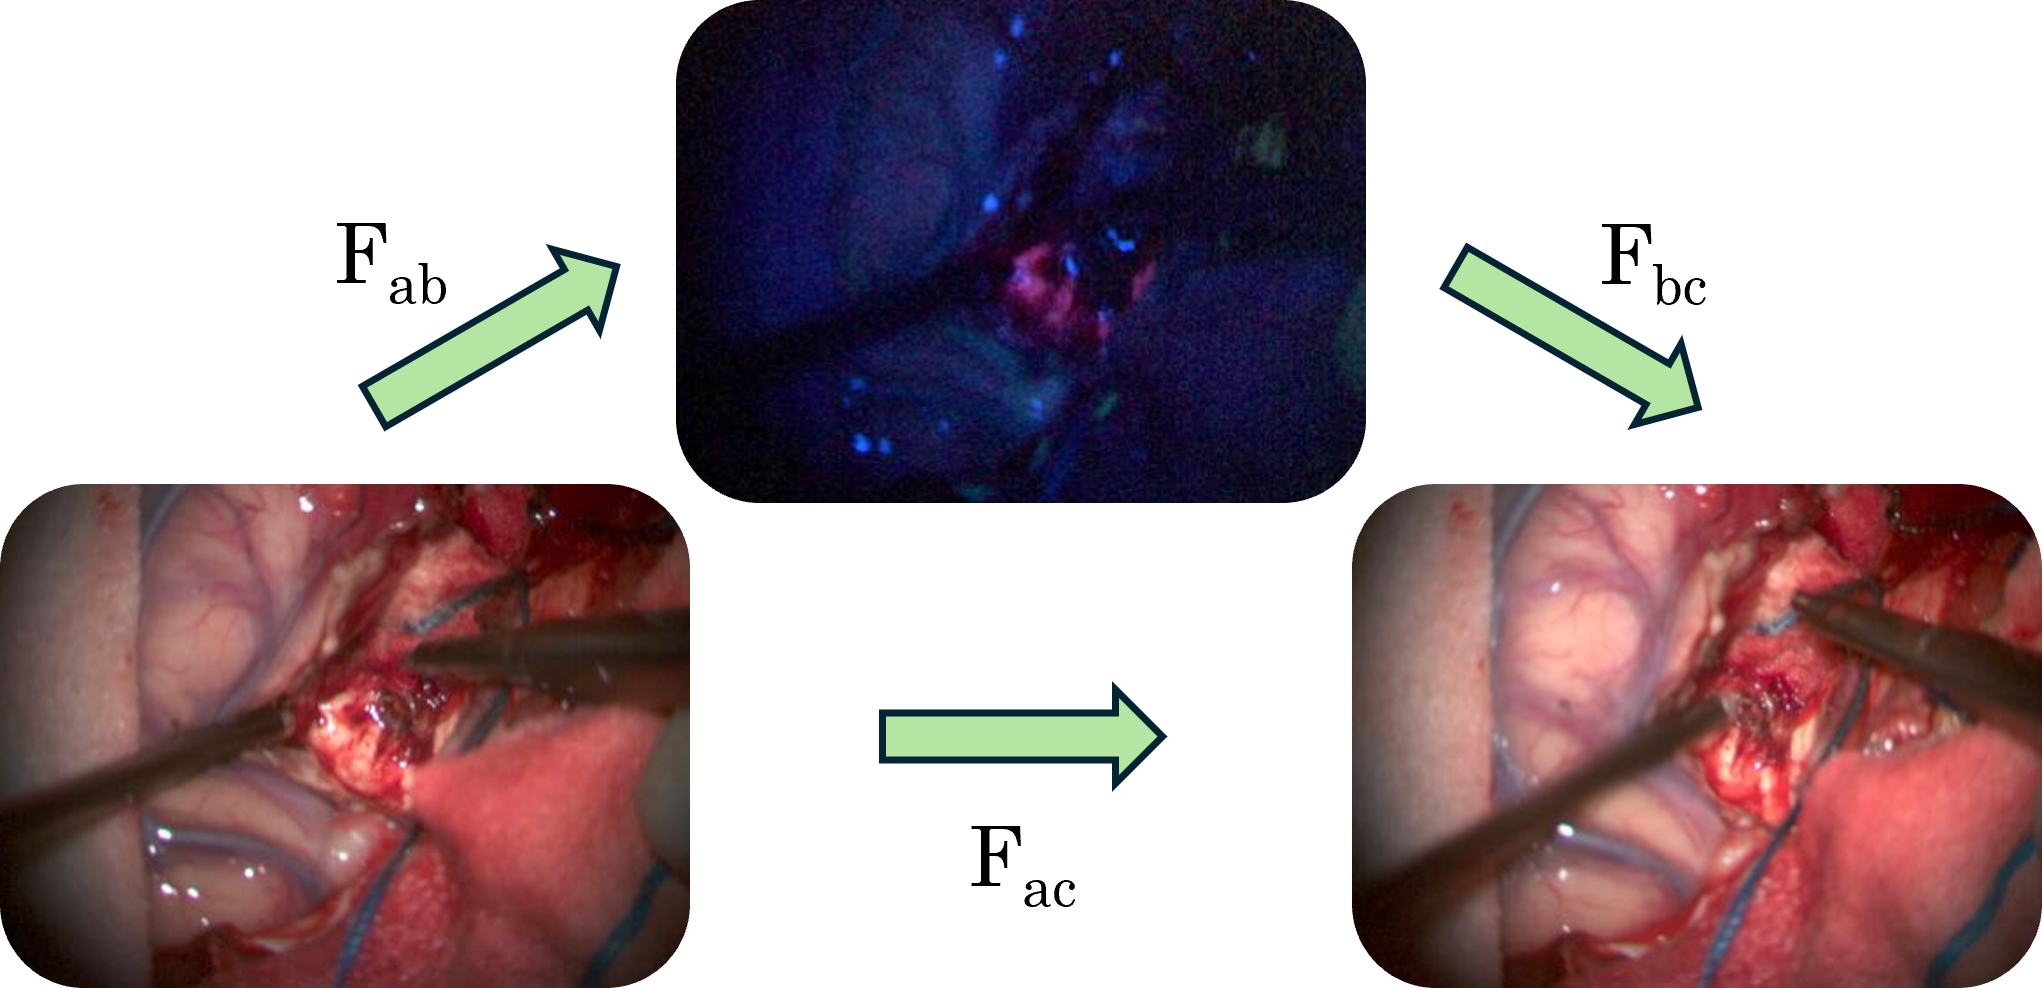

Figure 3: Depiction of the flow cycle-consistency triplet for our self-supervision X-RAFT training. Optical flow inferred between the two white images, using off-the-shelf RAFT, is used as supervision for training of the white-to-blue and blue-to-white flow.

As we lack ground truth optical flow for our data, we require a self-supervised training strategy. Typical methods in optical flow rely on either flow consistency or photometric constancy. In our case, photometric constancy is inappropriate as the image pairs would not be expected to be visually similar after registration. As such, we choose to design a flow consistency based learning objective. We take advantage of the fact that we posses multiple white light images of each scene, between which we may infer reliable optical flow using off-the-shelf pre-trained RAFT. We therefore construct a flow cycle around a triplet constituting of two different white images and a blue image sampled from the same video, depicted in Fig. 3. Our loss function may then be expressed as the Euclidean distance between the vectors in the two optical flow fields, known as the end point error (EPE):

L=EPE(Fab+warp(Fbc,Fab),Fac)𝐿EPEsubscript𝐹𝑎𝑏warpsubscript𝐹𝑏𝑐subscript𝐹𝑎𝑏subscript𝐹𝑎𝑐L=\text{EPE}(F_{ab}+\text{warp}(F_{bc},F_{ab}),F_{ac})italic_L = EPE ( italic_F start_POSTSUBSCRIPT italic_a italic_b end_POSTSUBSCRIPT + warp ( italic_F start_POSTSUBSCRIPT italic_b italic_c end_POSTSUBSCRIPT , italic_F start_POSTSUBSCRIPT italic_a italic_b end_POSTSUBSCRIPT ) , italic_F start_POSTSUBSCRIPT italic_a italic_c end_POSTSUBSCRIPT ) (3)

where Fijsubscript𝐹𝑖𝑗F_{ij}italic_F start_POSTSUBSCRIPT italic_i italic_j end_POSTSUBSCRIPT represents the optical flow from the image Iisubscript𝐼𝑖I_{i}italic_I start_POSTSUBSCRIPT italic_i end_POSTSUBSCRIPT to the image Ijsubscript𝐼𝑗I_{j}italic_I start_POSTSUBSCRIPT italic_j end_POSTSUBSCRIPT, and warp(A,F)warp𝐴𝐹\text{warp}(A,F)warp ( italic_A , italic_F ) pulls pixels in the entity A𝐴Aitalic_A backwards along the flow field F𝐹Fitalic_F through grid sampling. Spatial correspondences between two images may not exist everywhere or information may be missing to extract them meaningfully. Our training objective is thus adapted by attempting to mask out such regions. One main consideration is occlusion induced by motion between frames. A typical approach for determining occluded regions is to calculate the optical flow in both directions. If true correspondences are found, the flow fields should have low discrepancy: